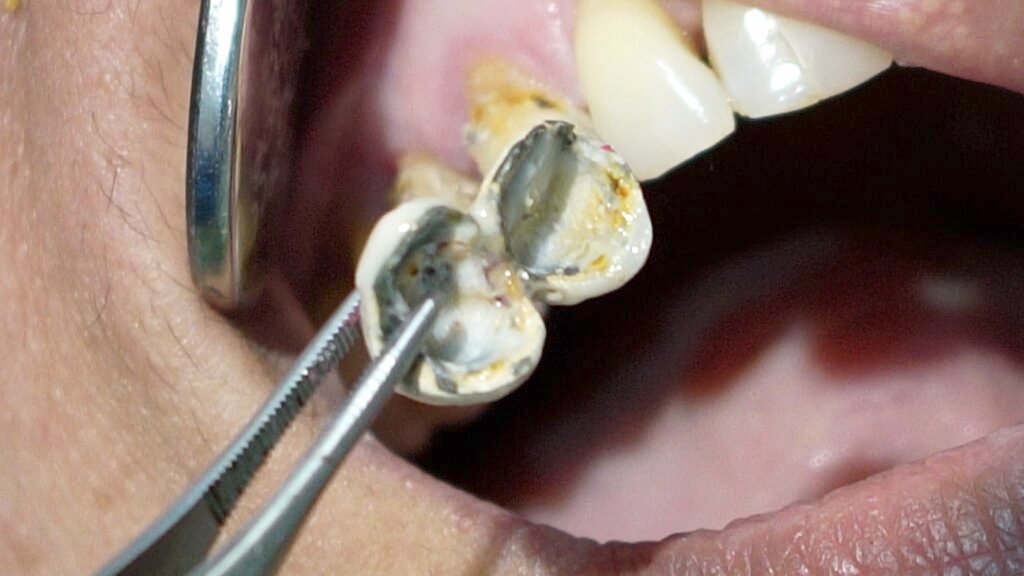

I explained the situation to the patient, noting that the tooth had been treated improperly and both the tooth and broken file would need to be removed. After removing the porcelain crown, I found that the restoration underneath was temporary and that dental caries were not properly cleaned out—an important first step before any root canal treatment

I then extracted the tooth, which showed overfilled canals, but unfortunately, the broken file did not come out with the tooth. A follow-up X-ray confirmed the file remained in the bone. Using a high-magnification microscope and special illumination, I performed a surgical procedure to carefully remove the broken file from the bone. The patient’s discomfort was resolved after a few days, and she recovered well.